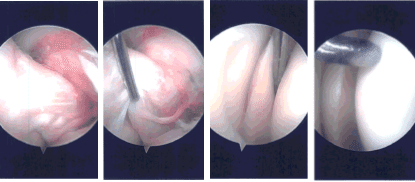

Había una compleja desgarro del cuerno posterior y del cuerpo del menisco medial hasta la superficie medial, así como el margen libre lateral. El desbridamiento del desgarro se realizó con el uso de mordedor y afeitadora, logrando un margen estable.

El artroscopio se insertó desde la porta de entrada medial y se limpió el margen del menisco medial hasta quedar equilibrado. Se tomaron y guardaron las fotos finales.

Imágenes de artroscopia intraoperatoria